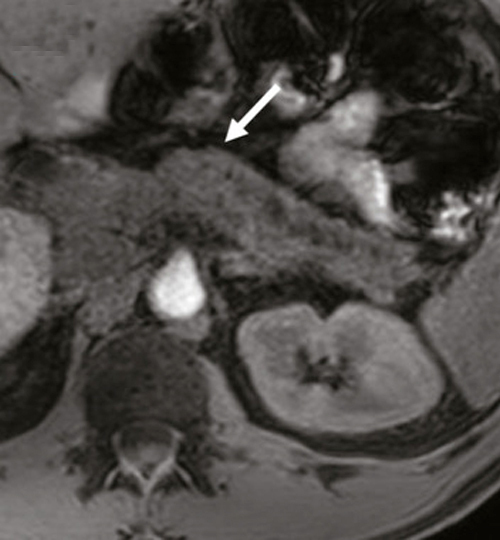

La pancréatite chronique se caractérise par des altérations morphologiques irréversibles du tissu exocrine et endocrine, associant inflammation et fibrose. C’est un continuum évoluant sur de nombreuses années. La pancréatite chronique est le fruit d’interactions multiples entre la consommation chronique d’alcool et de nicotine ; et des facteurs héréditaires, obstructifs, immunologiques et métaboliques. Quelle qu’en soit la cause prédominante, l’histoire naturelle et les complications restent similaires, seuls varient leur délai et leur fréquence d’apparition : insuffisance pancréatique exocrine et endocrine, douleurs chroniques, cancer du pancréas. Un bilan morphologique doit être réalisé, associant une scanographie et une pancréato-IRM. L’échoendoscopie permet le diagnostic des formes précoces et la recherche de diagnostics différentiels devant une forme focale pseudotumorale.